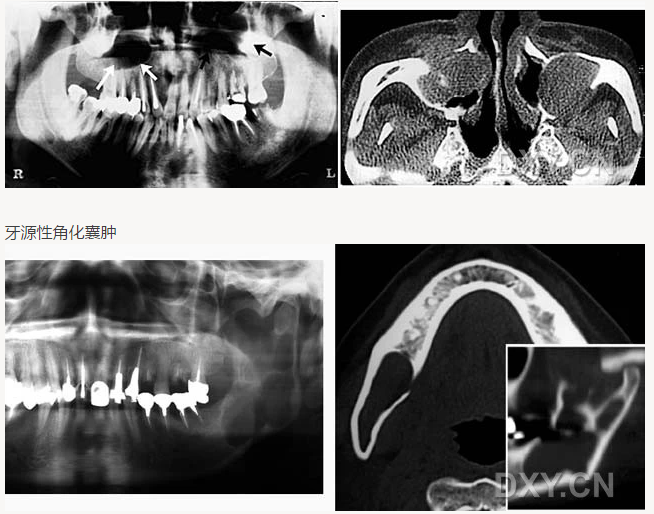

頜骨骨折

牙源性角化囊腫